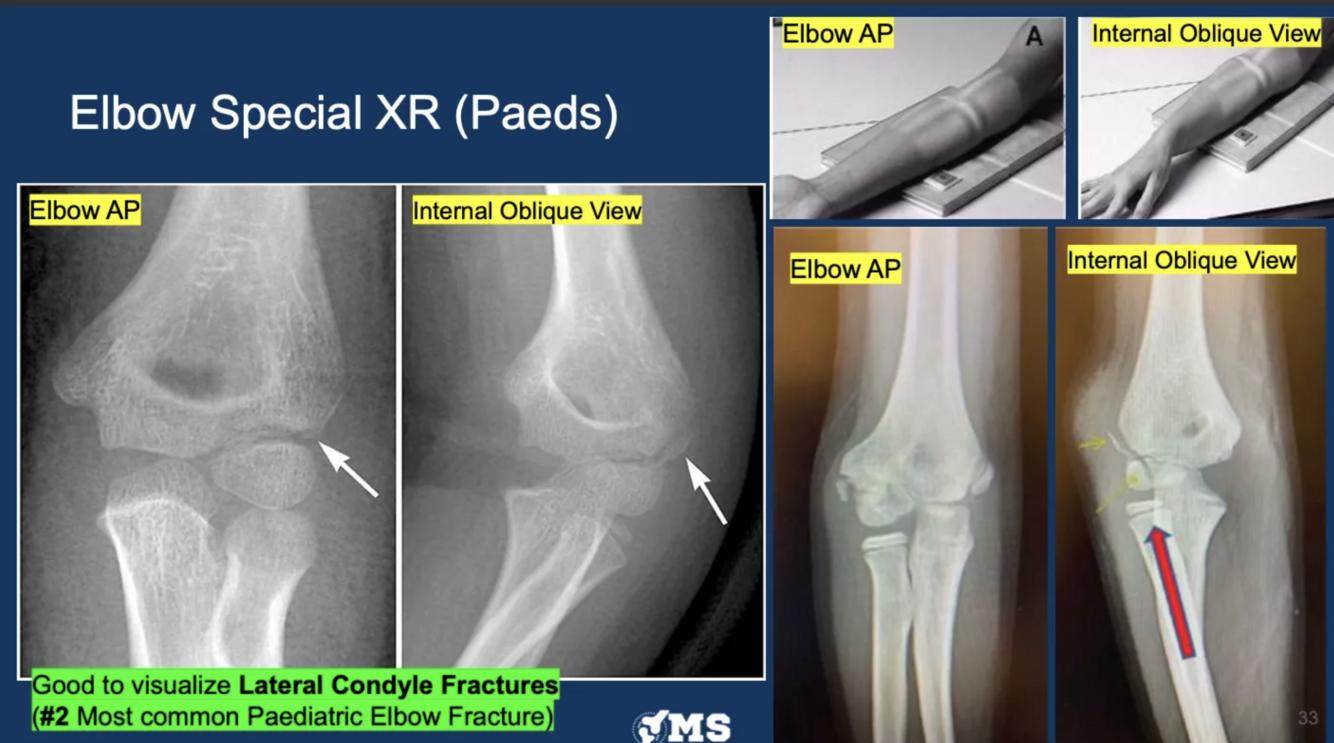

What elbow XR view do we use to visualise a lateral condyle fracture?

internal oblique view